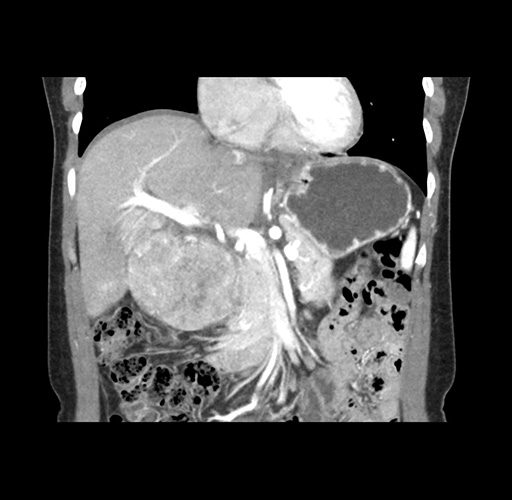

Imaging Analysis

Look through the patient's CT scan to identify any areas of concern for the necessary procedure.

Based on your CT findings, which issue(s) would give reason for "planned slowing down moment(s)" in this case?

Considering a standard left lateral sectionectomy procedure, what step(s) of the operation would you do differently in this case ?